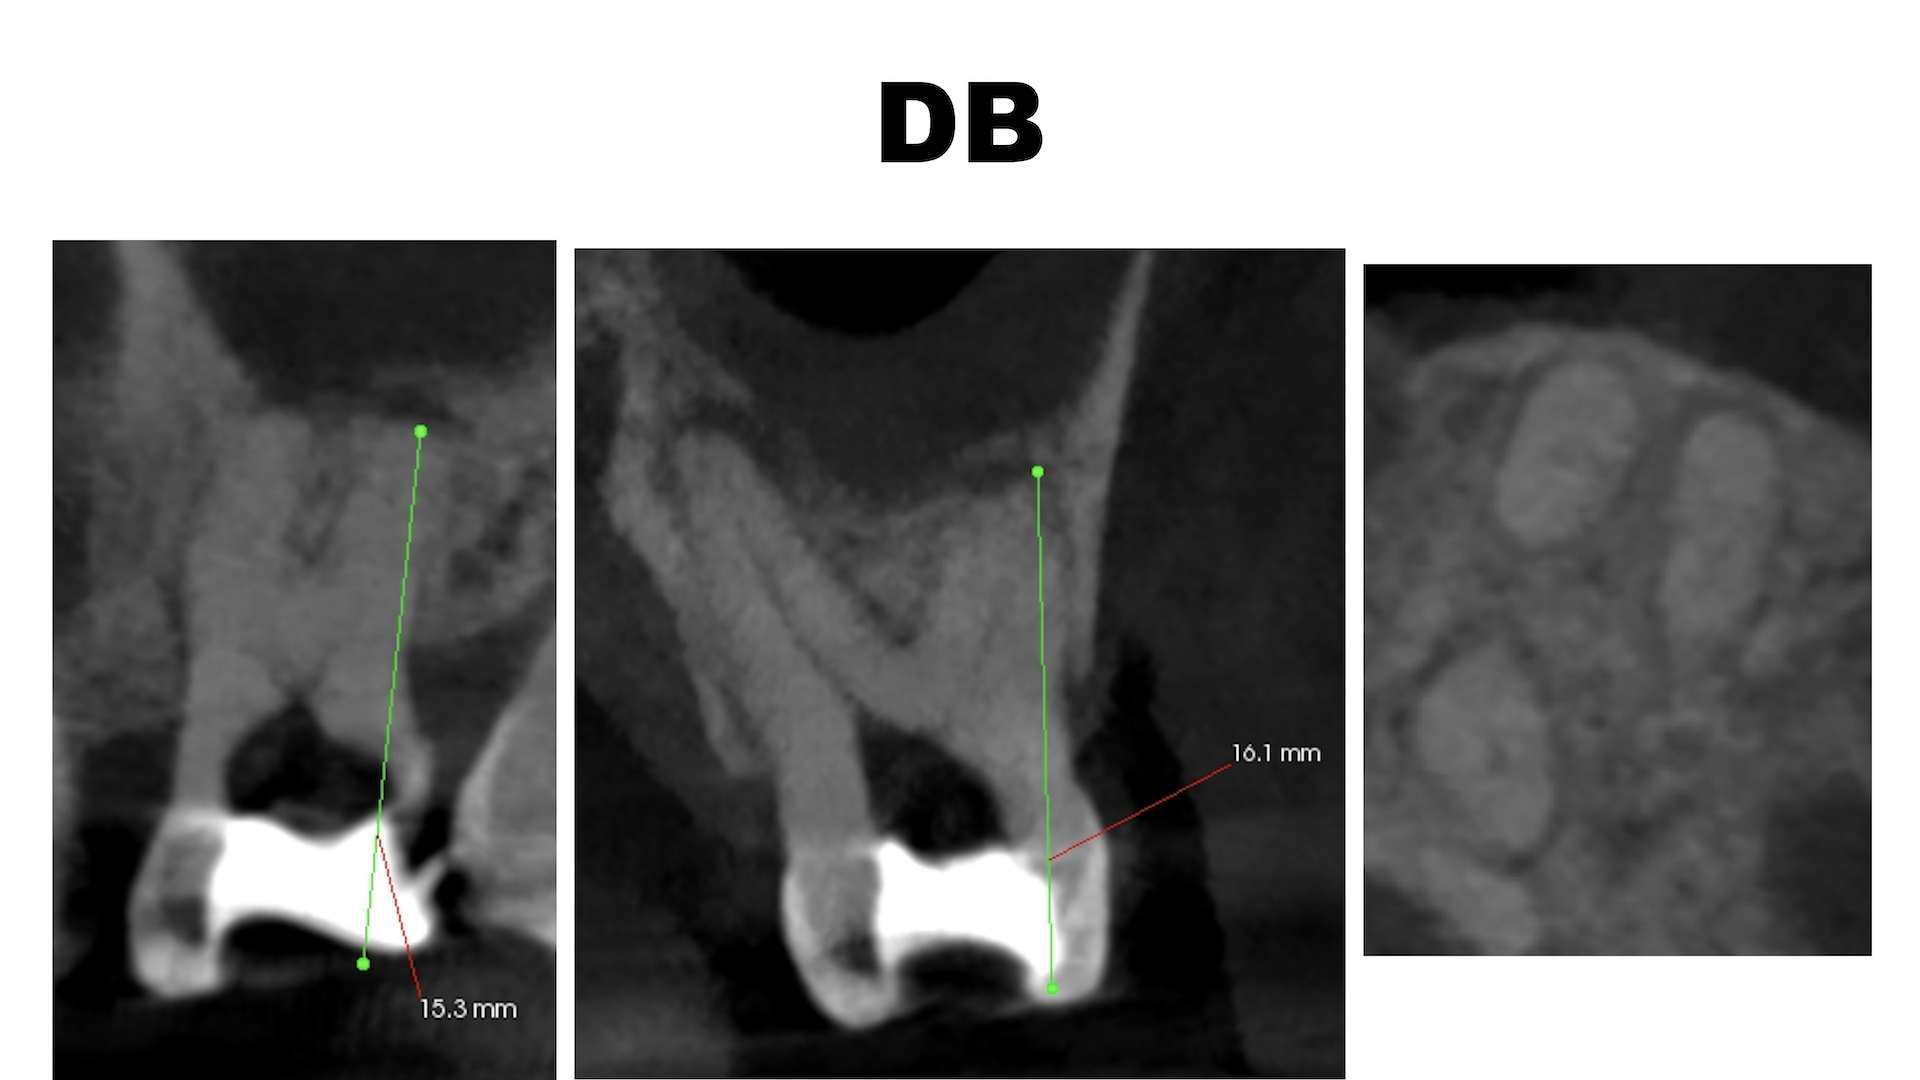

DB

ということで、術後にPA, CBCTを撮影した。

#14